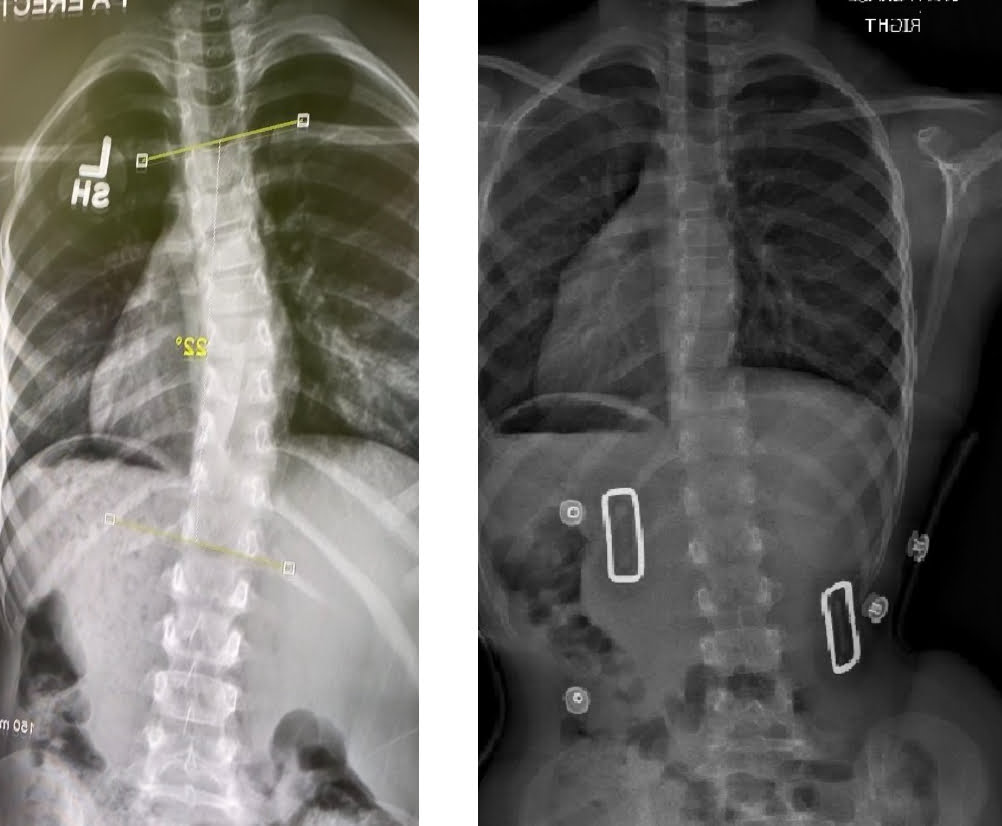

إذا تم بالفعل تشخيص إصابتك بالجنف فسوف تحتاج إلى إحضار صورة أشعة سينية حديثة لعمودك الفقري. يتم إثبات وجود الجنف عن طريق قياس زاوية كوب لمنحنيات العمود الفقري.

تم وصف زاوية كوب لأول مرة في عام 1948 من قبل الدكتور جون آر كوب، وهو جراح عظام أمريكي. تعتبر زاوية كوب التي تبلغ 10 درجات هي الحد الأدنى للزاوية لتحديد الجنف.

ستعتمد توصياتنا بشأن علاج اعوجاج العمود الفقري على شدة زاوية كوب وعمر المريض. وهذا يسمح لنا بحساب معامل تقدم المنحنى وتحديد الخطه العلاجيه الأكثر ملاءمة لكل مريض. نحن نأخذ في الاعتبار أيضًا نمط حياة الفرد وأعراضه.

تعتمد الخطه العلاجيه والمنهج الطبي المتبع على زاوية كوب للمريض :

- 10-20 درجة – التصحيح الذاتي المكثف والمبادئ العلاجيه الخاصه بشروث (العلاج الطبيعي المتخصص) والتصحيح الزائد لوضعية الجسم: لهدف وقف تطور هذه الانحناءات أو تقليلها (اعتمادًا على نضج العظام).

- 20-25 درجة – المراقبة عن كثب وتوفير نفس البرنامج مع مراقبة دقيقة للتقدم ولكن البدء في الاخذ بعين الاعتبار تقويم الجنف باستخدام حزام اعوجاج العمود الفقري PioBrace (اعتمادًا على نضج العظام).

- أكثر من 25 درجة – سيحتاج طفلك لتقويم فعال للجنف باستخدام حزام اعوجاج العمود الفقري PioBrace جنبًا إلى جنب مع التصحيح الذاتي المكثف و الطرق العلاجبيه المعتمده على مبادئ شروث (العلاج الطبيعي المتخصص).